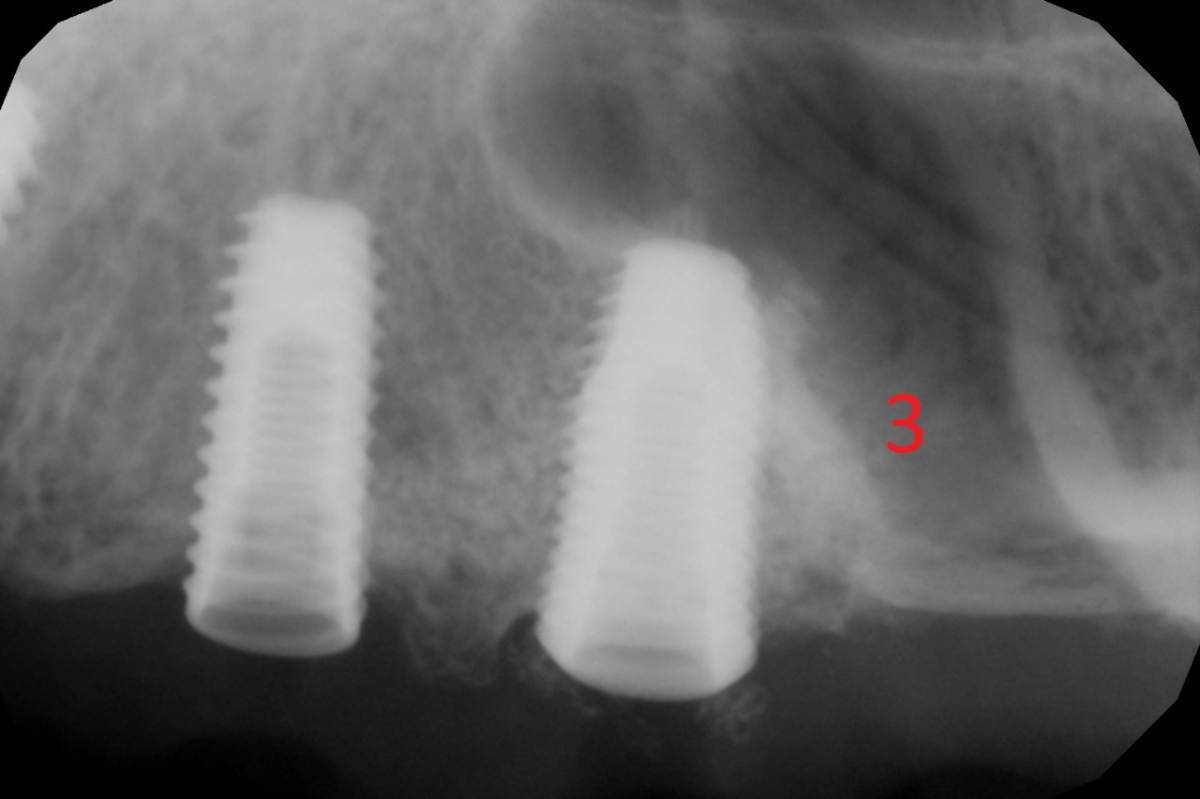

Помогите пожалуйста определить систему имплантов. Доков никаких нет, ставили +- 10 лет назад, ставил в одном месте , у одного врача. (это всё у одного пациента). Номерами подписал винты, которыми были прикручены коронки к имплантам. Винт от 2,3,4 снимка имплантов очень похож на имплантиум. Но сами импланты вроде не похожи на имплантиум. винт под номером один похож на ICX , но опять таки...импланты не признаю на снимке. Кто что думает?

3 похожи на дентиум, 4 на осстем тс4, 5 - на любой клон spi альфы, хотя соединение вроде бы конус